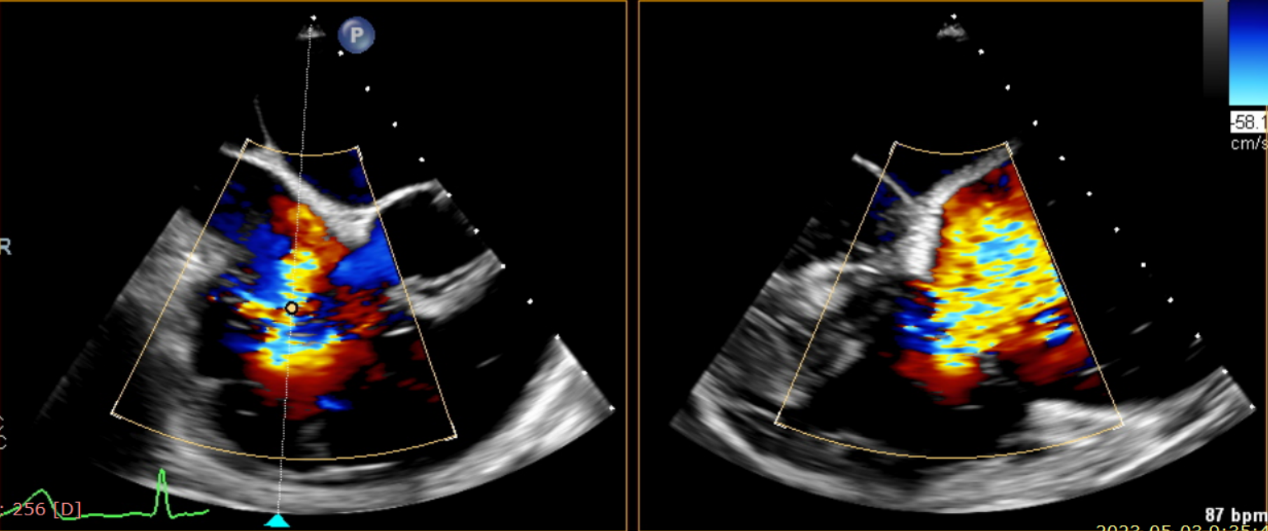

術(shù)前超聲提示大量三尖瓣反流

術(shù)后超聲提示僅殘余輕微瓣周漏